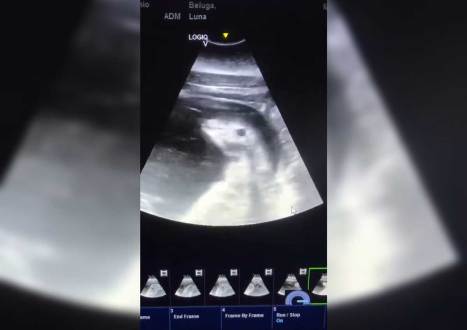

The abusement park company took to social media on January 11 to flex its speciesist muscles, posting a sonogram depicting the unborn baby of Luna, a beluga whale who has been confined at SeaWorld San Antonio for more than two decades.